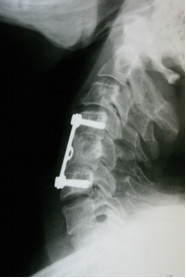

Przedstawiony obraz rtg przedstawia: